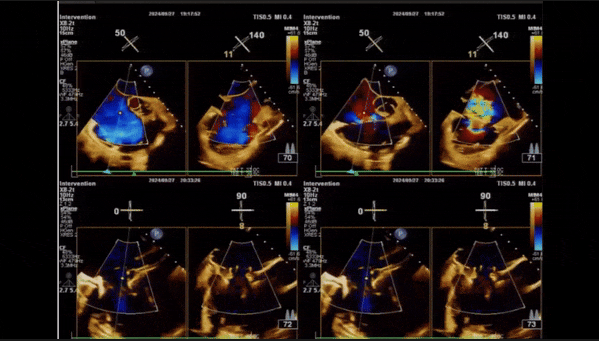

術(shù)后即刻返流

術(shù)中經(jīng)食道超聲輔助下可見LuX-Valve Plus夾持件抓捕瓣葉狀態(tài)良好,夾持件在位,室間隔錨定位置良好,假體瓣膜整體錨定狀態(tài)穩(wěn)固。

術(shù)后即刻經(jīng)食道超聲可見,三尖瓣假體瓣膜位置合適,牛心包瓣葉運(yùn)動狀態(tài)良好,開閉正常,瓣周及瓣葉對合緣處未見明顯返流,心電圖及心包狀態(tài)較術(shù)前無明顯變化。

術(shù)前術(shù)后返流情況對比